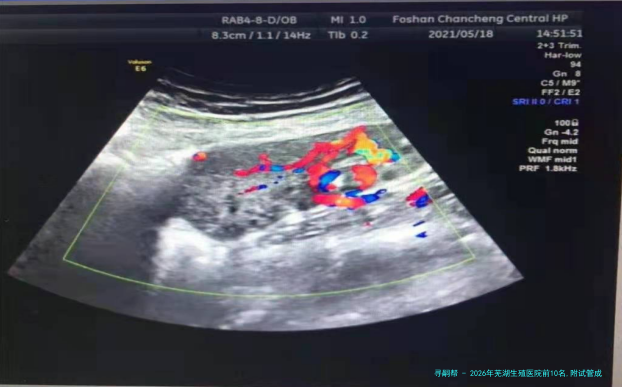

2026年芜湖生殖医院前10名,附试管成功率较高的医院

全国助孕试管婴儿线上

在线解答 足不出户 视频交流 科学备孕